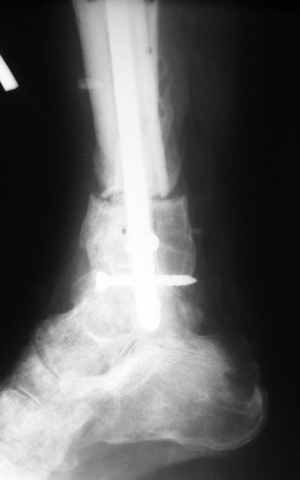

Ерсин, мы тоже имеем опыт такой фиксации. Подобную операцию за последние 3 года мы сделали трем пациентам. Снимки одного из них я прилагаю.

К сожалению, ни в одном из этих 3-х случаев мы не получили удовлетворяющего нас результата. Очень трудно провести штифт, введенный антеградно ровно по центру таранной кости. Отсутствие подвижности между диафизом и дистальным отломком большеберцовой кости (после фиксации в аппарате в течение 1-2 мес) очень усложняет проведение штифта в центр блока таранной кости. Поэтому мы от этого пока отказались, и проводим штифт через пятку. При данном варианте фиксации подобных проблем не возникало ни разу.